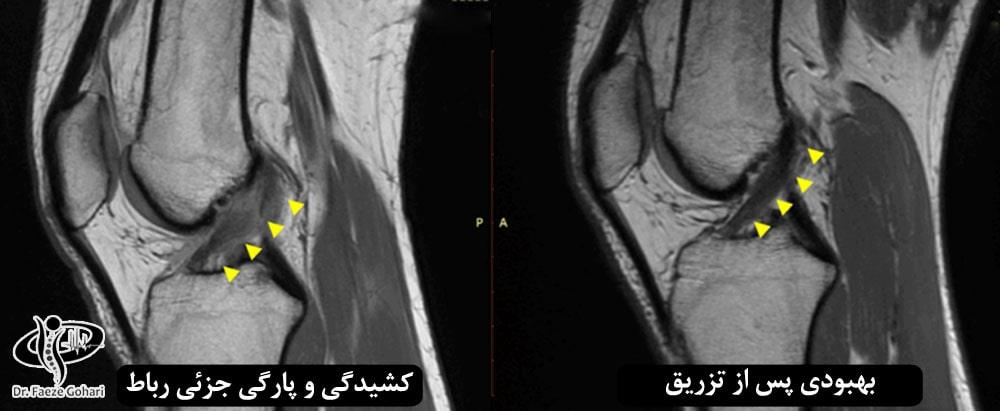

درمان پارگی رباط صلیبی، بهویژه برای افرادی که خواهان بازگشت سریع به فعالیتهای ورزشی هستند، اهمیت بسیاری دارد. بااینحال، بسیاری از بیماران پس از جراحی همچنان با مشکلاتی مانند بیحسی، درد، و محدودیت حرکتی زانو روبرو هستند. تزریق سلولهای بنیادی و PRP بهعنوان یک روش نوین، امید تازهای برای بازسازی طبیعی زانو و تسریع بهبودی فراهم کرده است. اغلب بیماران تنها ۷۲ ساعت پس از تزریق کاهش چشمگیری در علائم مشاهده میکنند و پس از ۶ ماه بهراحتی به ورزش بازمیگردند. این روش، بسته بهشدت آسیب، ممکن است به ۲ تا ۳ نوبت تزریق نیاز داشته باشد که با فاصلههای ۴ هفتهای انجام میشود. با این درمان پیشرفته، میتوانید بازگشت به زندگی پرتحرک و بدون درد را با اطمینان تجربه کنید.

پس از تزریق سلولهای بنیادی، علائم بهبودی در هفتههای اول بهوضوح مشاهده میشود، اما روند ترمیم تا ۶ ماه ادامه دارد تا رباط به استحکام و دوام کافی برسد. این فرایند به عواملی مانند سن بیمار و رعایت دقیق دستورالعملهای پزشکی پس از تزریق بستگی دارد.

طبق شواهد علمی، برای درمان پارگی رباط صلیبی با سلولهای بنیادی، احتمالاً به ۲ تا ۳ جلسه تزریق نیاز است که در فواصل زمانی مشخص (مثلاً هر ۴ تا ۶ هفته) انجام میشود تا بهترین نتایج در ترمیم رباط و بافتهای آسیبدیده حاصل شود. تعداد دقیق جلسات بسته به شرایط فردی بیمار، شدت آسیب و نوع درمان متغیر است. هزینه درمان نیز بر اساس تعداد جلسات و شدت آسیب بیمار برآورد میشود.